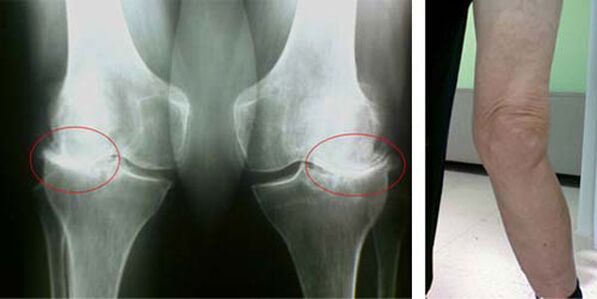

Σε μια υγιή άρθρωση γόνατος, ο χόνδρος είναι ένα είδος επένδυσης που δεν επιτρέπει στα οστά να αγγίξουν, επομένως, εξαλείφοντας την πιθανότητα βλάβης κατά το περπάτημα. Ο άρρωστος χόνδρος δεν μπορεί να αντιμετωπίσει αυτή τη λειτουργία, επομένως, εμφανίζονται σημάδια ακαμψίας στην άρθρωση κατά τη διάρκεια της κίνησης, συνοδευόμενα από πόνο. Αυτή η κατάσταση γίνεται μόνιμη λόγω εσωτερικών παθολογικών αλλαγών, όταν η λέπτυνση του χόνδρινου ιστού οδηγεί σε πάχυνση του οστού και δημιουργεί συνθήκες για την εμφάνιση οστικών σπιρουνιών - οστεοφύτων, που προκαλούν οξύ πόνο.

Τα αρχικά στάδια της εμφάνισης μιας τέτοιας παθολογίας όπως η αρθροπάθεια της άρθρωσης του γόνατος δεν εκδηλώνονται οπτικά με κανέναν τρόπο. Ωστόσο, μετά από ορισμένο χρονικό διάστημα, ο ασθενής παρατηρεί σημάδια παραμόρφωσης στο γόνατο, καθώς και μια χαρακτηριστική καμπυλότητα κατά μήκος του άξονα της κνήμης (κατευθυνόμενη προς τα μέσα). Υπάρχει επίσης ένα τραγανό όταν πρέπει να λυγίσετε το πόδι.

Η παρουσία πόνου, περιορισμένης κίνησης στο γόνατο κάνει ένα άτομο να δει γιατρό και να υποβληθεί σε εξέταση. Για να γίνει αυτό, πρέπει να περάσει εξετάσεις και να κάνει ακτινογραφία της πάσχουσας άρθρωσης. Εάν αυτά τα μέτρα δεν είναι αρκετά για να επιβεβαιώσουν την αρθροπάθεια της άρθρωσης του γόνατος, τότε γίνεται μαγνητική τομογραφία. Με βάση τα δεδομένα που συλλέγονται, ο γιατρός επιλέγει τις καλύτερες μεθόδους θεραπείας.